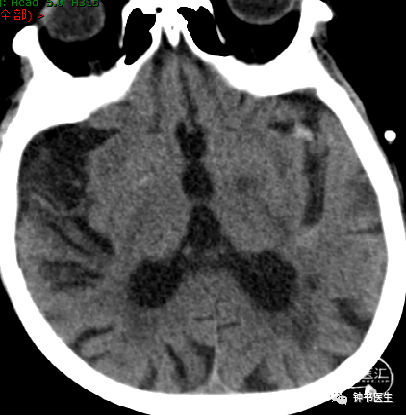

2012-11-8 CT

左颞部脑梗加重,出血渗出点增多。继续加强镇静镇痛治疗。

2012-11-10 CT

病情趋稳定,转出监护室治疗。